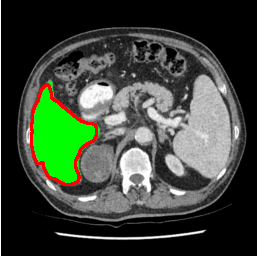

Our primary findings comparing the proposed model to baseline fully-supervised models when segmenting the liver from the LiTS dataset are reported in Table 1. The reported results demonstrate that our SAM-Mix model consistently achieves higher Dice scores compared to the fully supervised baselines as well as the two-stage SAM-PP method. Against U-Net, the best-performing fully supervised method, the SAM-Mix variant trained on 50 segmentation labeled slices (SAM-Mix-50), achieves a Dice score improvement of 5.9%. In terms of Hausdorff distance, while the fully-supervised baselines do slightly outperform SAM-Mix-5 and SAM-Mix-100, SAM-Mix-50 does achieve a lower Hausdorff distance by 22.38%. Qualitative evaluation as shown in Figs. 3 further affirms the superiority of SAM-Mix over baseline and existing fully-supervised methods as well as the two-stage SAM-PP variants. Furthermore, the boxplot visualization in Fig. 2 showcases consistently improved performance by SAM-Mix outperforming all the fully supervised and semi-supervised methods.